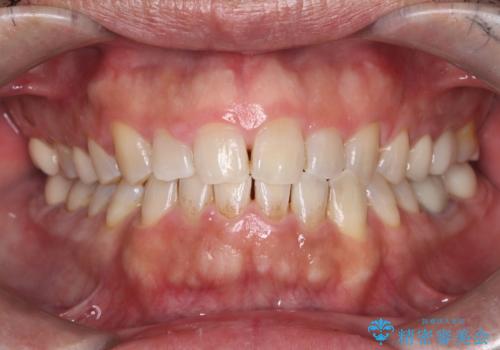

前歯の突出を防ぎながらガタつきを解消。上下左右4番抜歯による審美ワイヤー矯正

担当医 河口智英